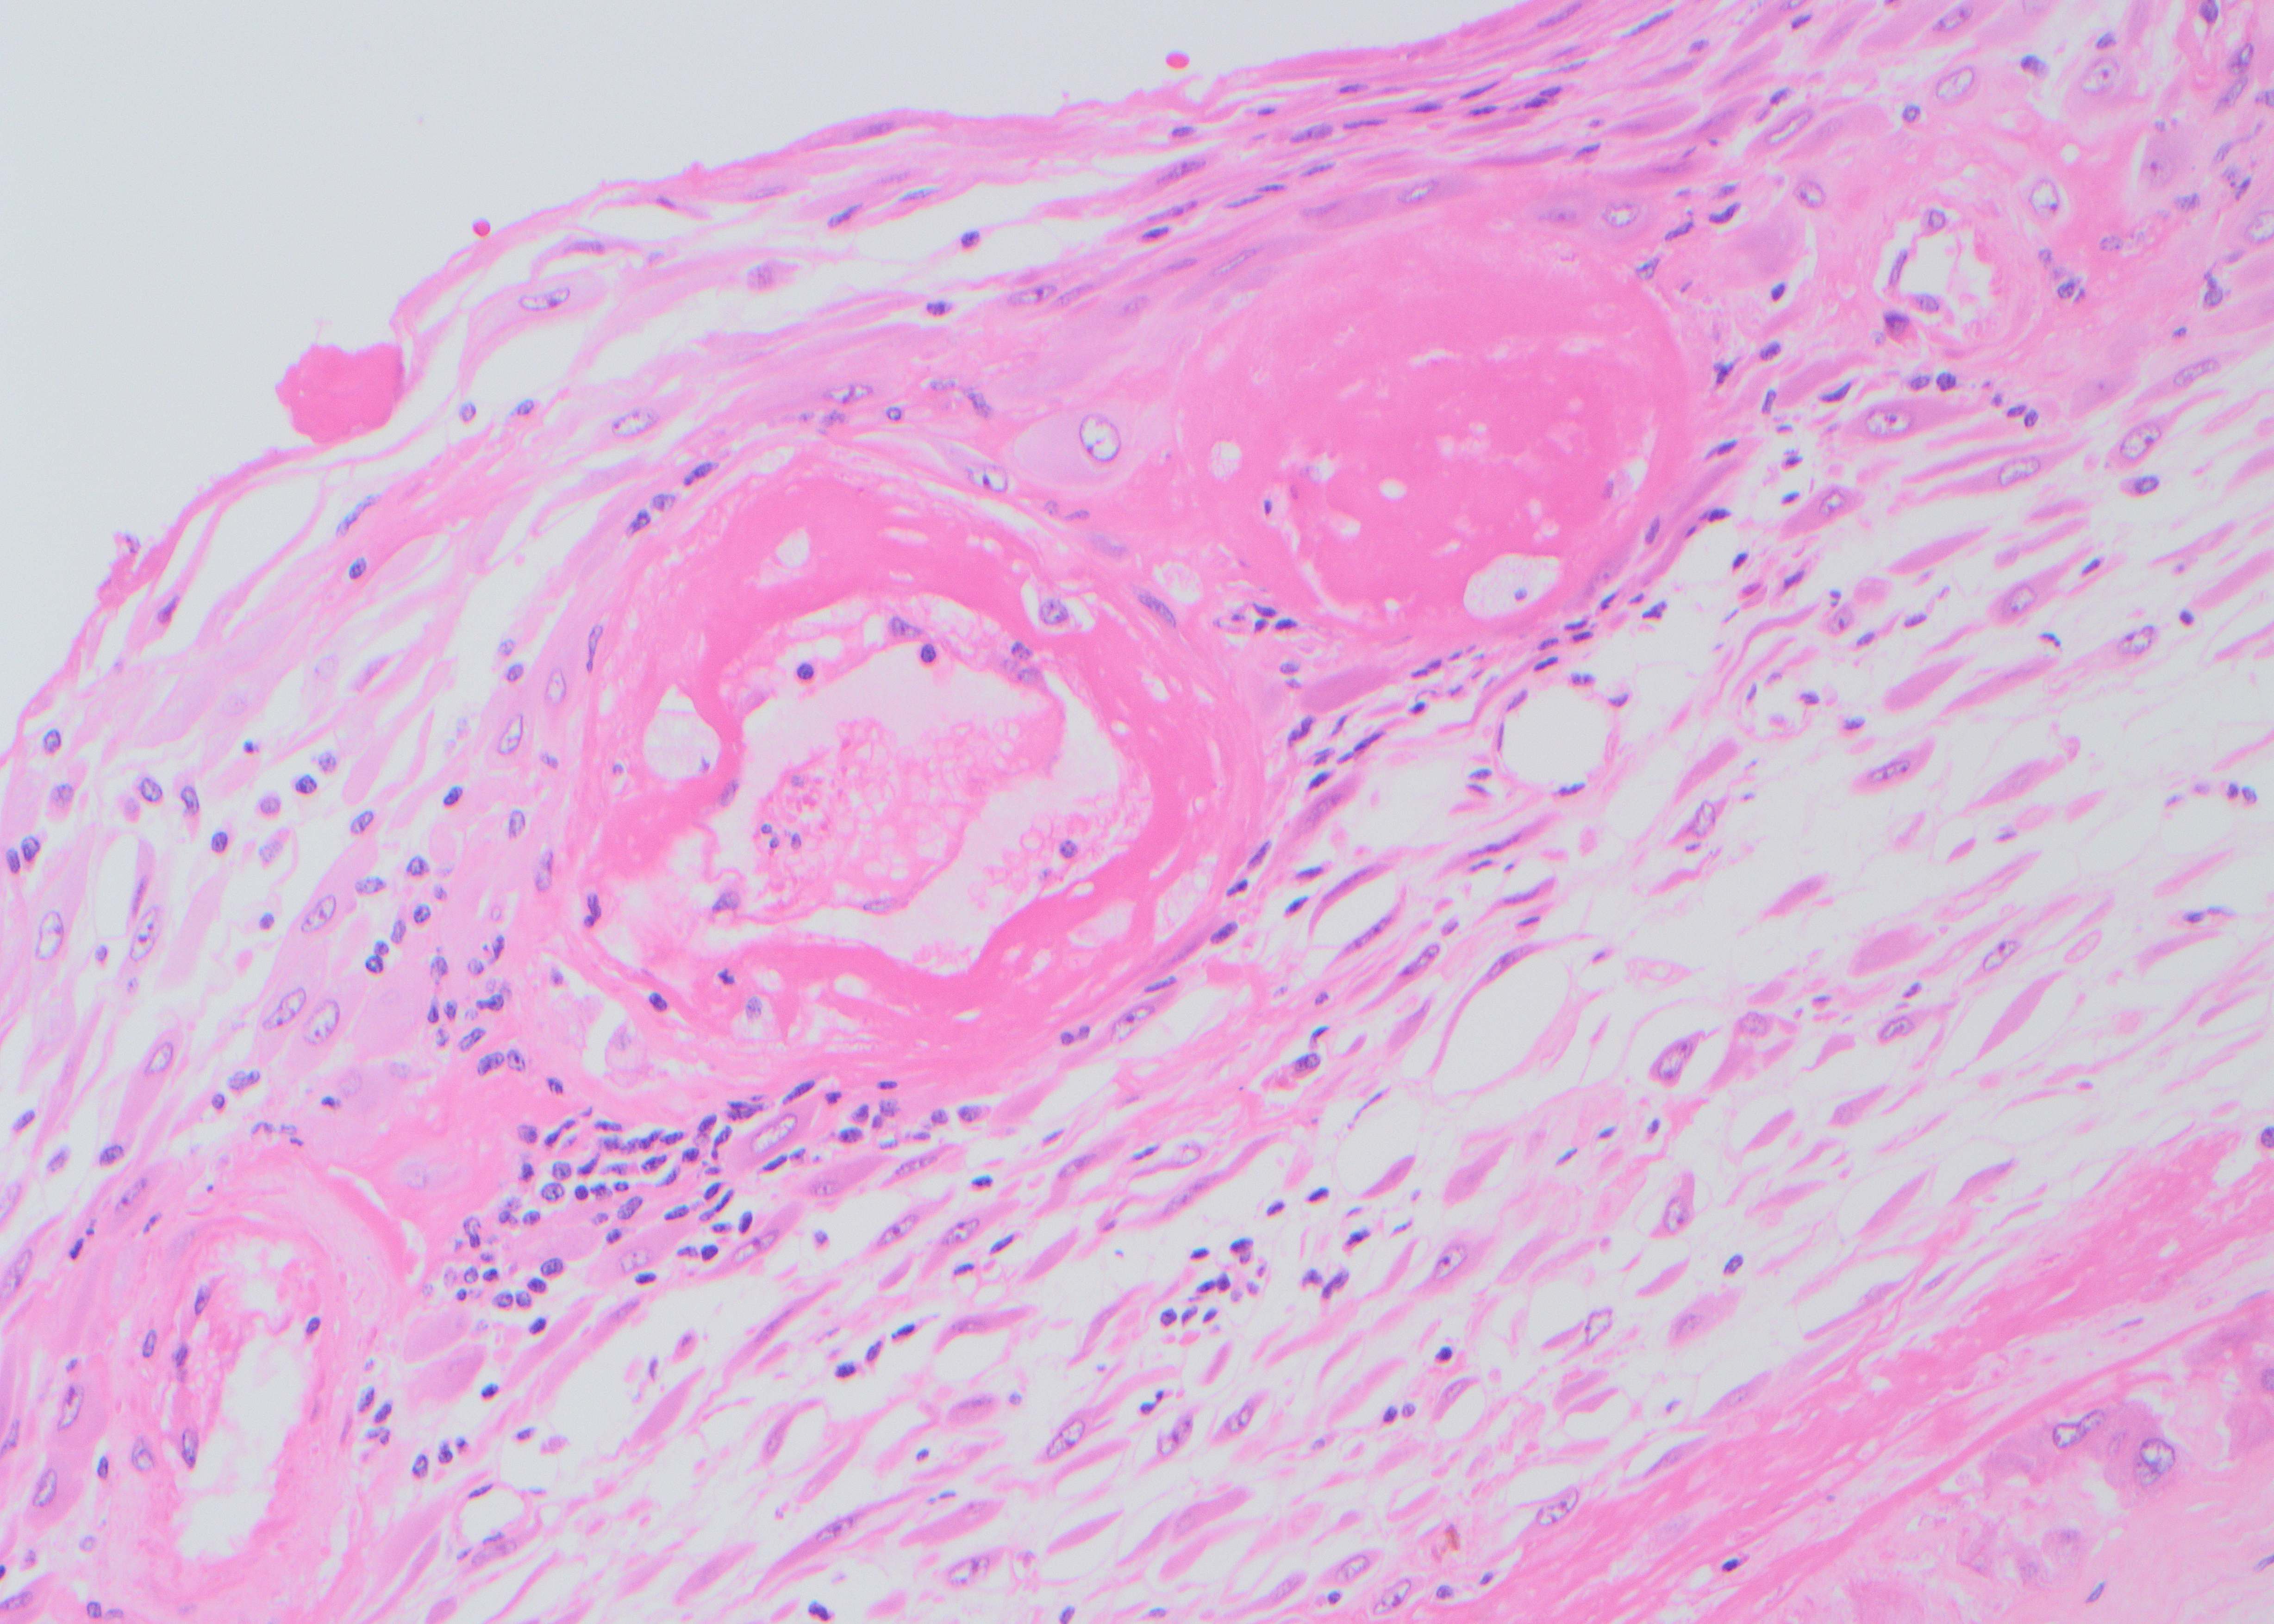

A male patient in his mid-thirties with a personal and family history of polyps underwent duodenal polypectomy.